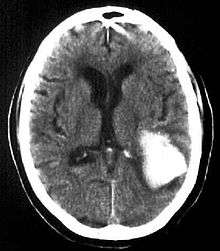

Intraparenchymal hemorrhage

Intraparenchymal hemorrhage (IPH) is one form of intracerebral bleeding in which there is bleeding within brain parenchyma. The other form is intraventricular hemorrhage (IVH).

Intraparenchymal hemorrhage accounts for approx. 8-13% of all strokes and results from a wide spectrum of disorders. It is more likely to result in death or major disability than ischemic stroke or subarachnoid hemorrhage, and therefore constitutes an immediate medical emergency. Intracerebral hemorrhages and accompanying edema may disrupt or compress adjacent brain tissue, leading to neurological dysfunction. Substantial displacement of brain parenchyma may cause elevation of intracranial pressure (ICP) and potentially fatal herniation syndromes.